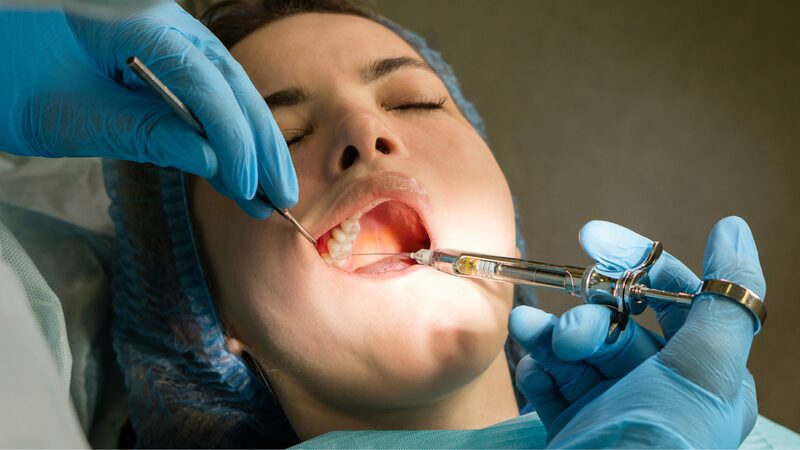

Kiểm tra tình trạng răng miệng định kỳ

Việc kiểm tra tình trạng răng miệng định kỳ không chỉ giúp phát hiện sớm các vấn đề mà còn đảm bảo rằng bạn đang thực hiện cách chăm sóc răng sau khi niềng một cách hiệu quả. Hãy lên lịch hẹn với bác sĩ nha khoa ít nhất 6 tháng một lần để kiểm tra sức khỏe răng miệng của mình.

Các bác sĩ sẽ kiểm tra xem có dấu hiệu nào của sâu răng, viêm nướu hoặc bất kỳ vấn đề nào khác không. Nếu phát hiện ra vấn đề, bác sĩ có thể cung cấp phương pháp điều trị kịp thời.

Tuân thủ lịch hẹn với bác sĩ để điều chỉnh và kiểm tra tiến trình

Mỗi bệnh nhân sẽ có thời gian tái khám khác nhau, tùy thuộc vào tình trạng răng miệng và kế hoạch điều trị của từng người. Tuy nhiên, việc tuân thủ lịch hẹn sẽ giúp bạn tiết kiệm thời gian và đảm bảo rằng quá trình niềng răng diễn ra suôn sẻ.

- Trong mỗi lần tái khám, bác sĩ sẽ kiểm tra sự di chuyển của răng và điều chỉnh lực kéo của khay niềng nếu cần thiết.

- Việc điều chỉnh này không chỉ giúp răng di chuyển đúng hướng mà còn giảm thiểu đau đớn trong quá trình điều trị.

Báo ngay các dấu hiệu bất thường: đau kéo dài, mách chảy, khay bị lệch

Nếu bạn gặp phải các triệu chứng bất thường như đau kéo dài, chảy máu nướu hay cảm thấy khay niềng bị lệch, hãy liên hệ ngay với bác sĩ. Không nên chờ đợi cho đến khi lịch hẹn tái khám để báo cáo vấn đề.